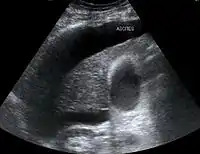

Хворим проводять ультразвукове дослідження органів черевної порожнини, при цьому оцінюють стан паренхіми печінки та судин системи ворітної вени, розміри органу. За необхідності проводять комп'ютерну рентгенівську томографію органів гепатопанкреатичної ділянки.